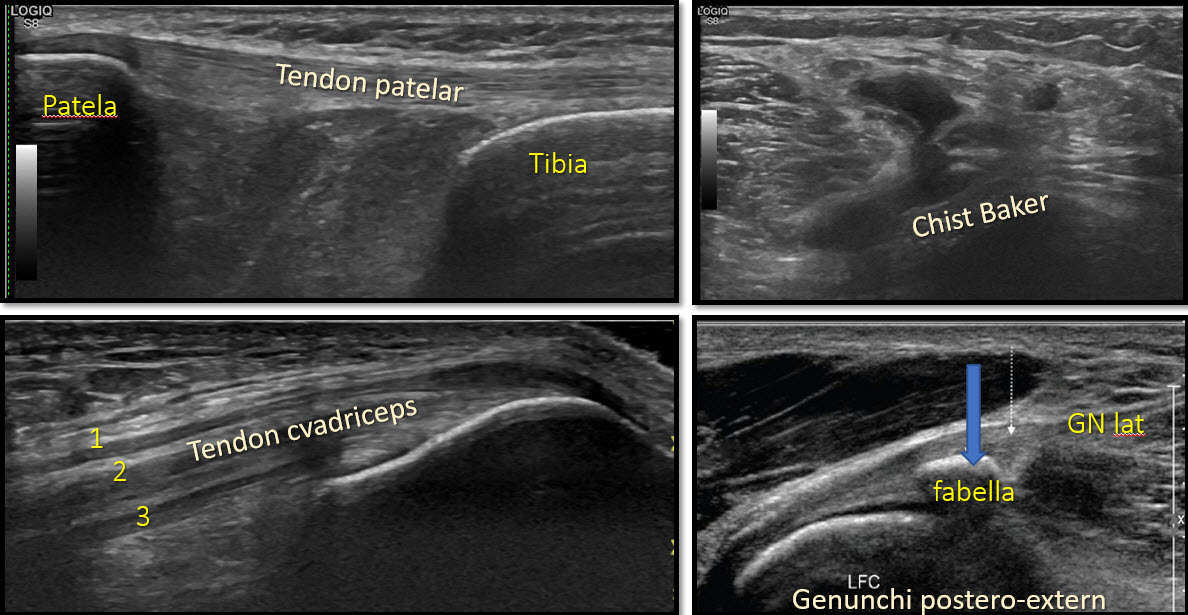

Rolul ecografiei în investigația genunchiului este limitat, comparativ cu rolul ecografiei în examinarea umărului. Astfel, ecografia poate detecta un număr limitat de structuri, în special superficiale, cum ar fi ligamentele colaterale, capsula, tendoanele. Leziunile meniscului, cartilajului sau a ligamentelor încrucișate, sunt nedetectabile ecografic, datorită interpunerii structurilor osoase, impenetrabile la ultrasunete. Mobilitatea redusă a genunchiului, comparativ cu a umarului, limitează astfel posibilitățile de explorare ecografică a genunchiului.

Ecografia devine foarte importantă în monitorizarea bolilor reumatologice, unde se pot efectua ecografii pre și post tratament și evidenția cantitatea de fluid intraarticular, grosimea și vascularizația sinovialei, prezența sau nu a eroziunilor marginale.

Examinarea ecografică a genunchiului

Avantajul major al ecografiei este posibilitatea de evidenția cu mare ușurință acumulările fluide intraarticulare, precum și sinoviala (cămașa articulară), fapt pentru care este deosebit de utilă în practica reumatologică.

Un avantaj suplimentar al ecografiei este faptul că permite focalizarea examinării exact asupra regiunii dureroase. În plus, ecografia se poate efectua în dinamică, mișcând membrul pacientului și comparându-l cu membrul contralateral, sănătos.

În cazul detecției patologiei inflamatorii intraarticulare/sinoviale, se poate lua decizia unei intervenții minim invazive (evacuare fluid intraarticular, chist Baker, injectare intraarticulară sau intrabursală de mix antiinflamator și analgezic) sub ghidaj ecografic.